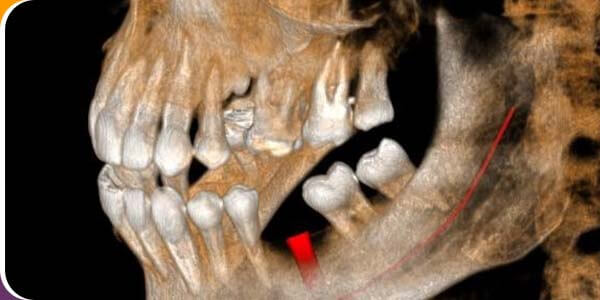

Treatment Begins with Diagnosis.OralMax™ CBCT (Cone Beam Computed Tomography) Scan is a specialized dental imaging technique that provides three-dimensional reconstruction of dental and associated maxillofacial structures (teeth, jawbone, and surrounding tissues) to your dentist. This visualization significantly augments your dentist's ability to relate clinical evaluation with your chief complaint by providing them with a comprehensive view aiding in precise diagnosis, treatment planning for procedures like implants and extractions, and a deeper understanding of your oral health. Consequently, the underlying cause of the dental concern, and subsequent fact-based treatment plan are enhanced through imaging tools.

Accurate diagnosis and treatment planning are the backbone of any medical and dental therapy; for this reason, cone beam computed tomography (CBCT) was introduced and has been widely used. CBCT technology provides a three-dimensional image viewing, enabling exact location and extent of lesions or any anatomical region. For the very same reason, CBCT is not only used for surgical fields but also for fields such as endodontics, prosthodontics, and orthodontics for appropriate treatment planning and effective dental care